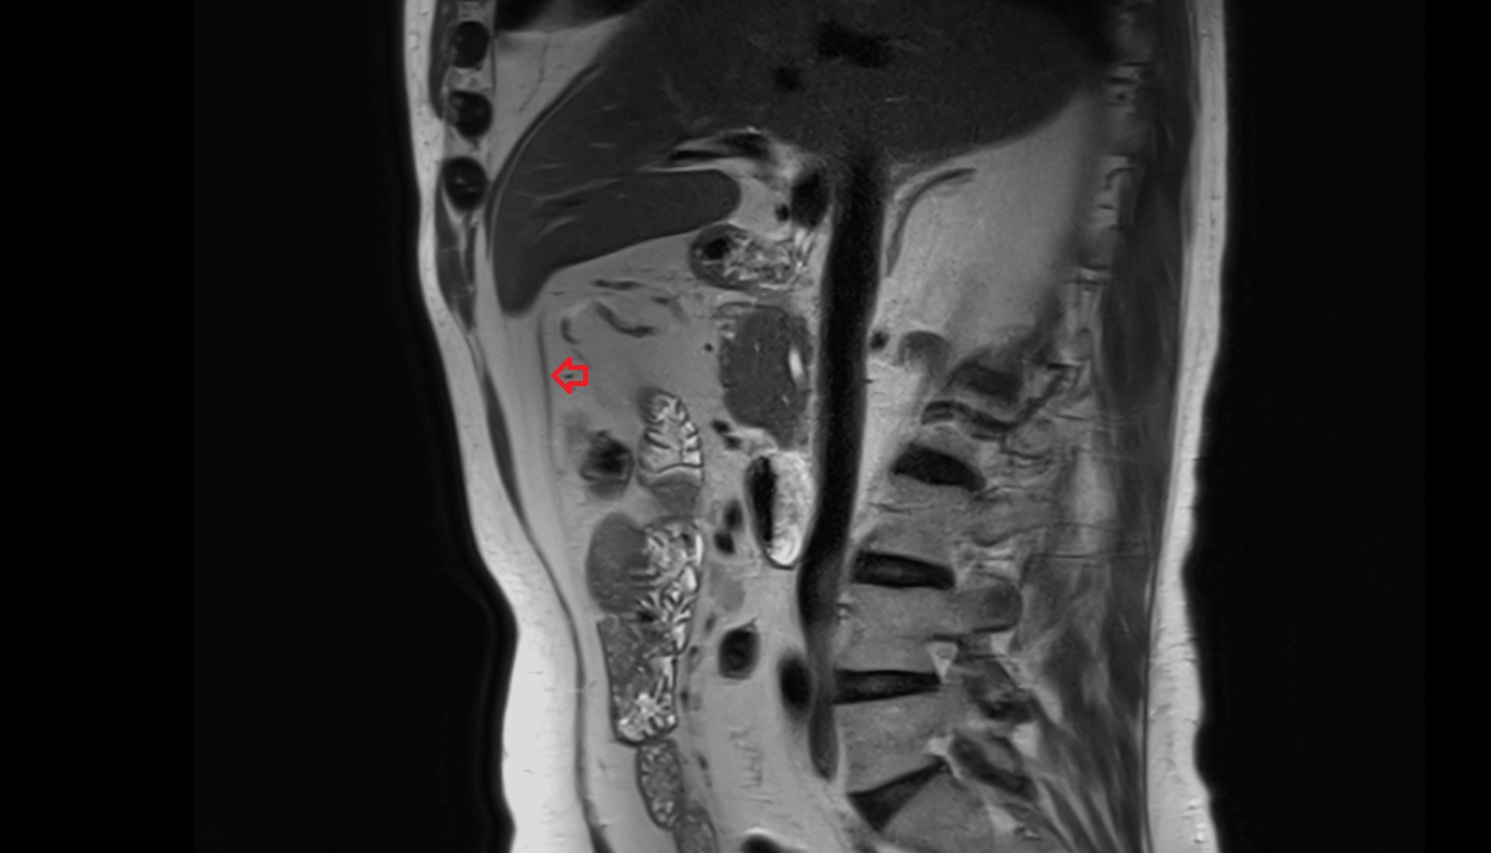

- Uterus

- Body of uterus

- Fundus of uterus

- Cervix of uterus

- Isthmus of uterus

- Endometrium of uterus

- Myometrium of uterus

- Perimetrium of uterus

- Junctional zone of uterus